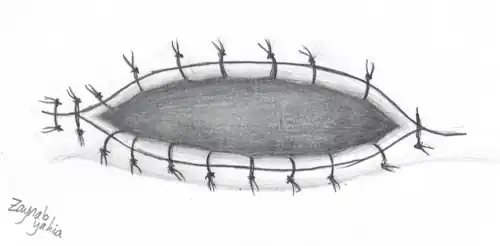

Panoramic(figure 1) and apical(figure 2) radiographs are commonly utilised in routine examinations to aid in the initial detection of BBC.[15] BBC is characterised by a well-defined radiolucent lesion on the buccal aspect of the tooth extending from furcation to the root apices.[19][20] With the presence of periosteal reaction on the buccal aspect of the tooth.[21][22] Tilting of the affected molars, with the apices of the roots tilted lingually and cusp tip buccally.[21][22] Unlike a periapical cyst, the periodontal ligament space and lamina dura remain intact and continuous, suggesting that the lesion is not directly associated with the root apices.[15][21][22]

Although uncommon, a BBC is a distinct condition that should be carefully considered as a differential diagnosis for a cystic lesion affecting a vital first or second mandibular molar in children and adolescents.[25] Over time, the treatment of BBC has evolved. It was stated that curettage of the cyst and tooth extraction were successful treatments.[5] The permanent dentition may be significantly impacted by the removal of the mandibular molar, hence a more conservative strategy that avoids tooth extraction was later adopted.[14][26] The marsupialization(figure 3) procedure has been successful in situations where enucleation could jeopardize the health of nearby teeth or cause harm to other nearby tissues such as nasal cavities, paranasal sinuses, and neurovascular bundles. It is recommended that the surgical exposure be large enough to provide proper clinical assessment of the cystic lining because marsupialization by design implies that a sizable amount of the cystic lesion will be retained by the jaws.[19]